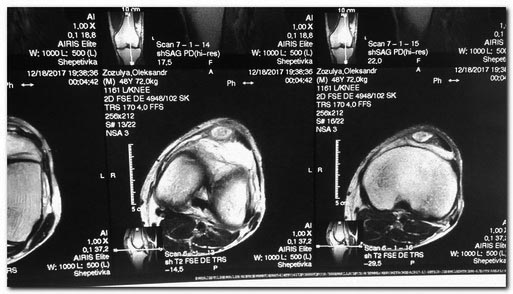

[Ortho] Остеомиелит надколенника

фото

Имя     : 1.jpg

Тип     : image/jpeg

Размер  : 57181 байтов

Url     : http://weborto.net:8080/pipermail/ortho/attachments/20171230/997926fb/attachment-0003.jpg